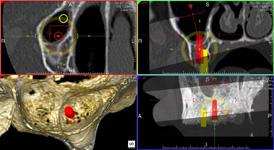

coDiagnostiX – Dental Wings

Jedná se o externí plánovací program, spojený se zubní laboratoří a frézovacím centrem, který využívá dat získaných z 3D rentgenu čelisti, otisku zubů a dásně (scanu zubů a dásně) a finálního návrhu protetické náhrady.

Tento program umožňuje tříprostorovou počítačovou simulaci při plánování pozic implantátů. Součástí programu je i databáze, ve které mohou být uloženy všechny typy implantátů od všech výrobců, včetně jejich délek, průměrů i tvarů.

Lékař si vytvoří všechny typy zobrazení potřebných pro naplánování – tedy 2D snímky (panoramatický), příčné řezy i 3D model.

Vidí zde i důležité anatomické útvary – čelistní dutinu, průběh nervu atd. Po proměření množství kosti – šířky i výšky vybere z databáze vhodný typ implantátu a umístí ho do požadované lokality. Ihned vidí jeho pozici ve všech 3 rovinách a na

všech snímcích i 3D modelu. Může upravovat podle potřeby jeho pozici, sklon atd.

Všechny vybrané a správně umístěné simulované implantáty se ukládají do „počítačové karty“ pacienta s jejich pozicí, délkou, průměrem, typem i sklonem. V programu také lékař navrhuje chirurgické šablony pro řízenou nebo navigovanou implantaci.

Lékař i pacient tedy ještě před vlastní operací vidí, jak by mělo ošetření probíhat a vypadat.